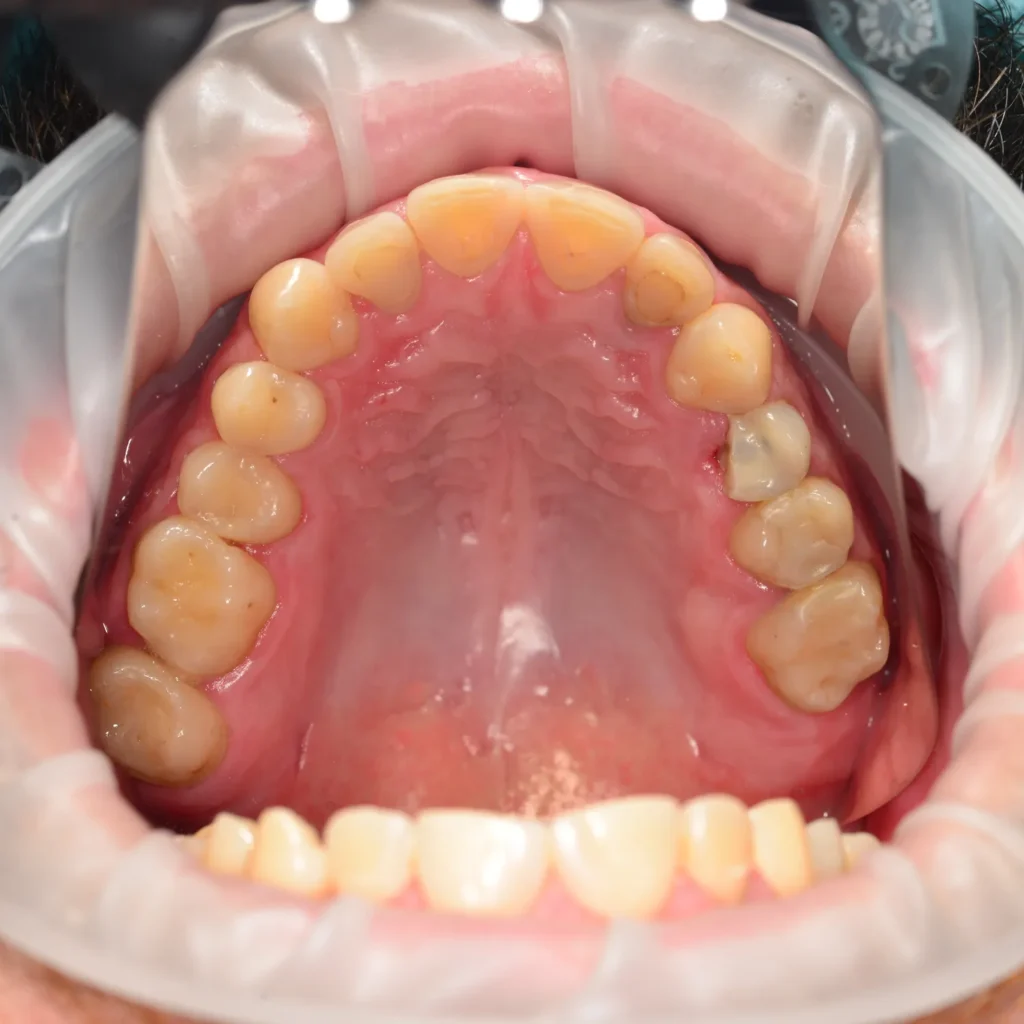

Пациент обратился с жалобами на короткие зубы, отсутствие нижних жевательных зубов и ограниченное открывание рта. Так как от установки брекетов пациент отказался, нами был предложен компромиссный вариант лечения. Было проведено поднятие высоты прикуса, создание новой формы зубов, установка имплантатов в жевательном отделе, закрытие всех зубов керамическими винирами.

На фото готовый результат спустя 6 месяцев эксплуатации.